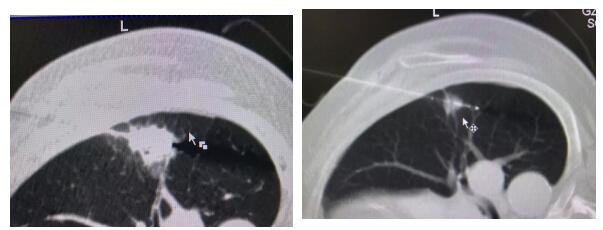

转眼到了三个月前,孙叔叔因感到有些胸闷,去体检的时候,发现他的右肺上有一个1.4厘米的结节,医生考虑是肺癌,随即为他为他做了活检,明确是一个神经内分泌大细胞癌。鉴于老人家的身体状况,医生认为他已经无法耐受麻醉和手术了,因为孙叔叔的肺功能非常差,走几步路就会喘,而且体重达到两百多斤,所以属于手术高危患者。

车到山前必有路。后来,经过省卫计委有关领导的介绍,孙叔叔来到了暨南大学附属复大肿瘤医院。复大肿瘤医院的专家立刻组织会诊,评估了老人家的身体状况,孙叔叔的病情还是比较严重的,病变本身不大,但是他的肺功能已经非常差。

不适合手术,也不适合化疗。经过讨论,复大的专家决定采取复大肿瘤医院的特色疗法,冷冻消融。在局麻下,将冷冻针刺入肿瘤中心,原地消融掉病灶;手术非常顺利,也没有痛苦,病灶被精准的消融掉了。